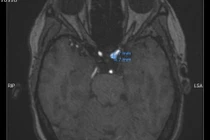

Túi phình mạch não là tình trạng thành động mạch não bị yếu và phồng lên tạo thành một túi nhỏ. Khi túi phình lớn dần, thành mạch trở nên mỏng và dễ vỡ.